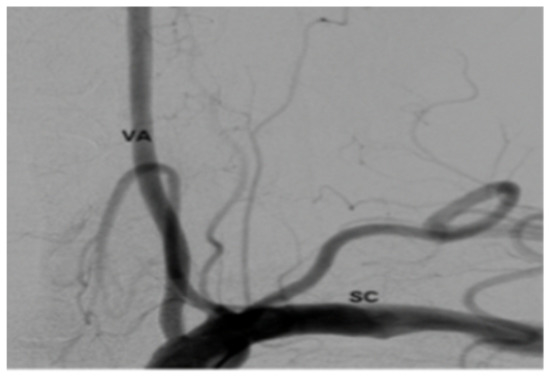

Plain X-rays revealed large anterior osteophytes most prominent from C4–C7 with severe spondylosis. MRI images show spinal cord compression from C4–C7 and myelomalacia at C5–C6, retrolisthesis at C4–C5, and severe multilevel disk degeneration (Figure 1).

Figure 1. Pre-op Sagittal Magnetic Resonance Image (MRI) (Cervical Spine).